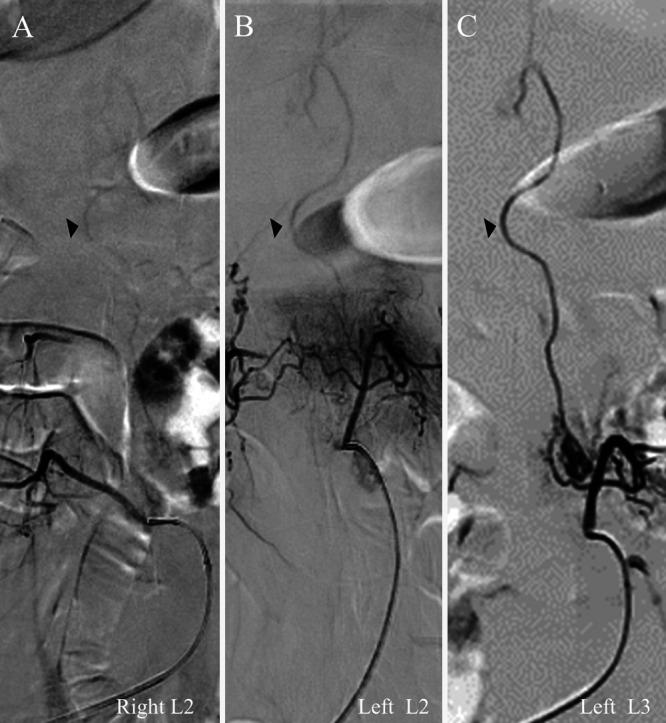

A 72-year-old man presented with progressive myelopathy due to a spinal epidural arteriovenous fistula. Spinal computed tomography angiography (sCTA) showed an epidural arteriovenous fistula fed by the left L3 segmental artery. To prepare for sDSA, the sCTA images were modified to mark the segmental artery bifurcations from T5 to L5 with multicolored markers. These modified sCTA images were loaded onto the multiwindow DSA display. The sCTA images were interactively modulated during sDSA. This sCTA-guided sDSA identified 18 segmental arteries within 47 minutes. The total radiation exposure was 1,292 mGy. Subsequently, transarterial embolization resolved the epidural arteriovenous fistula with clinical improvement.

一名72岁男性因脊髓硬膜外动静脉瘘出现进行性脊髓病。脊髓计算机断层扫描血管造影(sCTA)显示硬膜外动静脉瘘由左L3节段动脉供血。为准备sDSA,对sCTA图像进行修改,用多种颜色标记从T5到L5的节段动脉分支。这些修改后的sCTA图像被加载到多窗口数字减影血管造影(DSA)显示屏上。在sDSA过程中对sCTA图像进行交互式调节。这种sCTA引导的sDSA在47分钟内识别出18条节段动脉。总辐射暴露量为1292毫戈瑞。随后,经动脉栓塞术使硬膜外动静脉瘘得到解决,临床症状改善。